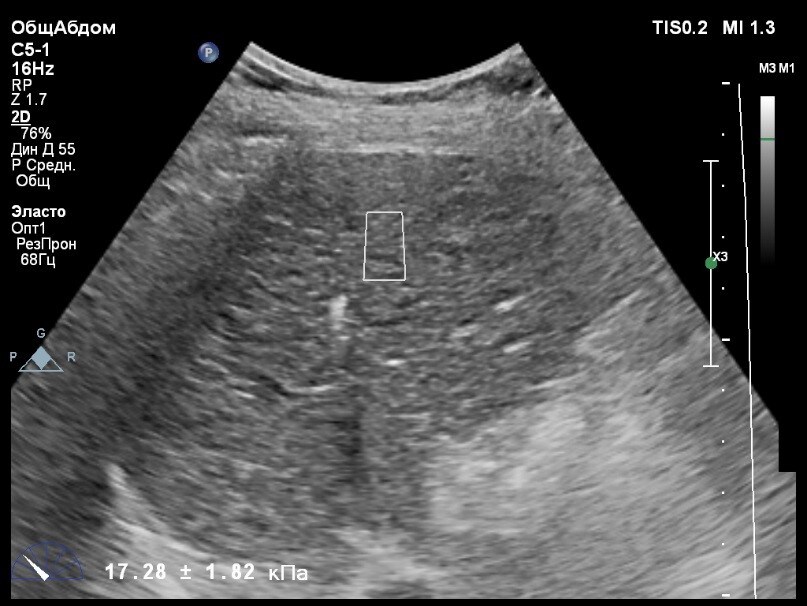

Пациент обратился к доктору с направлением на исследование степени жесткости печени в ноябре 2017 года. Из истории болезни, пациент страдает Гепатитом С с 2002 года. Закончила противовирусное лечение в мае 2017 года. В сентябре 2016 года, с помощью транзиентной эластографии была установлена медиана жесткости печени 45 kPA. На момент настоящего исследования, пациент не принимал пищу на протяжении 4 часов, АСТ, АЛТ не превышают патологических значений. В виду технических сложностей выполнения исследования (узкие межреберные промежутки), для оценки жесткости была выбрана технология компании Philips ElastPQ (точечная эластография) и прибор компании Philips Epiq 7. Исследование было проведено в соответствии с клиническими рекомендациями для ультразвуковых приборов компании Philips. В результате исследования были получены следующие результаты:

| 1 [17.28] kPa | 2 [13.59] kPa | 3 [14.47] kPa |

| 4 [16.71] kPa | 5 [18.48] kPa | 6 [21.20] kPa |

| 7 [21.36] kPa | 8 [15.64] kPa | 9 [19.95] kPa |

| 10 [19.89] kPa | 11 [22.14] kPa | 12 [16.48] kPa |

| 13 [16.41] kPa | 14 [22.02] kPa | |

Стандартное Отклонение [2.75] kPa Медиана Жесткости [17.88] kPa Фактор Качества IQR/Med 9%

Зона интереса расположена на более чем на один сантиметр глубже капсулы, параллельно ходу луча, в середине изображения, в участке печени лишенном артефактов.

Капсула видна как белая линия перпендикулярная ходу ультразвукового луча, исследования производятся приблизительно в одном и том же сегменте печени.

Для интерпретации полученных клинических данных были использованы Рекомендации по проведению эластографии сдвиговой волной для оценки жесткости печени при использовании ультразвуковых аппаратов компании Филипс с примером протокола. Следует отметить достаточно высокую жесткость печени у пациента по данным предыдущих обследований и низкую активность основного заболевания по данным биохимических проб, что является показанием для динамического наблюдения и оценки жесткости печени. Отмечу, что для проведения исследования у данного технически сложного пациента был совершенно обоснованно выбран аппарат экспертного класса. Подготовка пациента соответствовала проводимому исследованию. Представленные слайды проведенного исследования свидетельствуют о правильном техническом исполнении проб, что позволяет заключиться о достоверности полученных измерений. Таким образом, учитывая полученную медиану жесткости на уровне 17,88 кРа (13.59 -22.02 kPa) и уровень стандартных отклонений не превышающих 30%, полагаю, что уровень степени фиброза соответствует стадии F4. Заведующий отделением УЗД МЦ «Асклепий», Глушенко Д. Е.